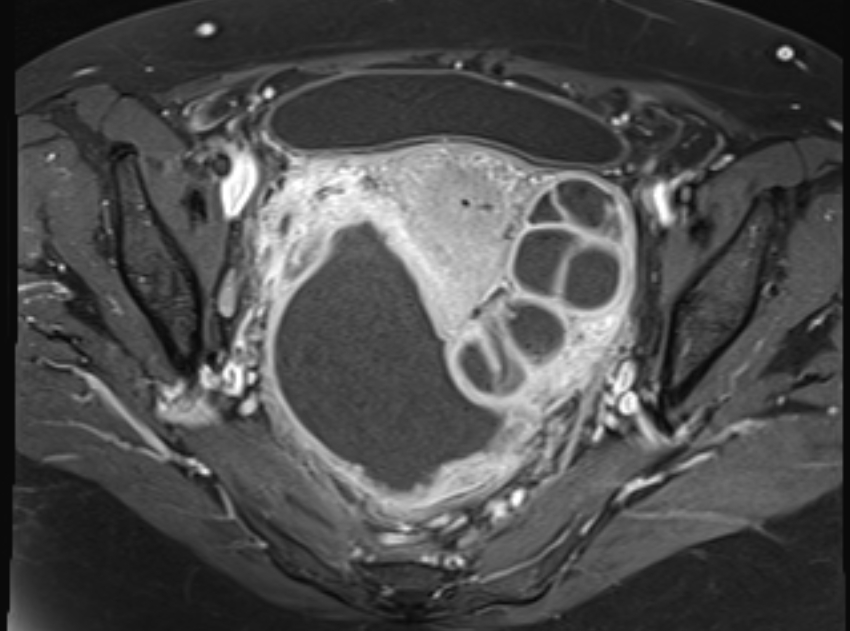

КТ диагностика тубоовариального абсцесса: Подходы и изображения

Раздел: Объективный взгляд